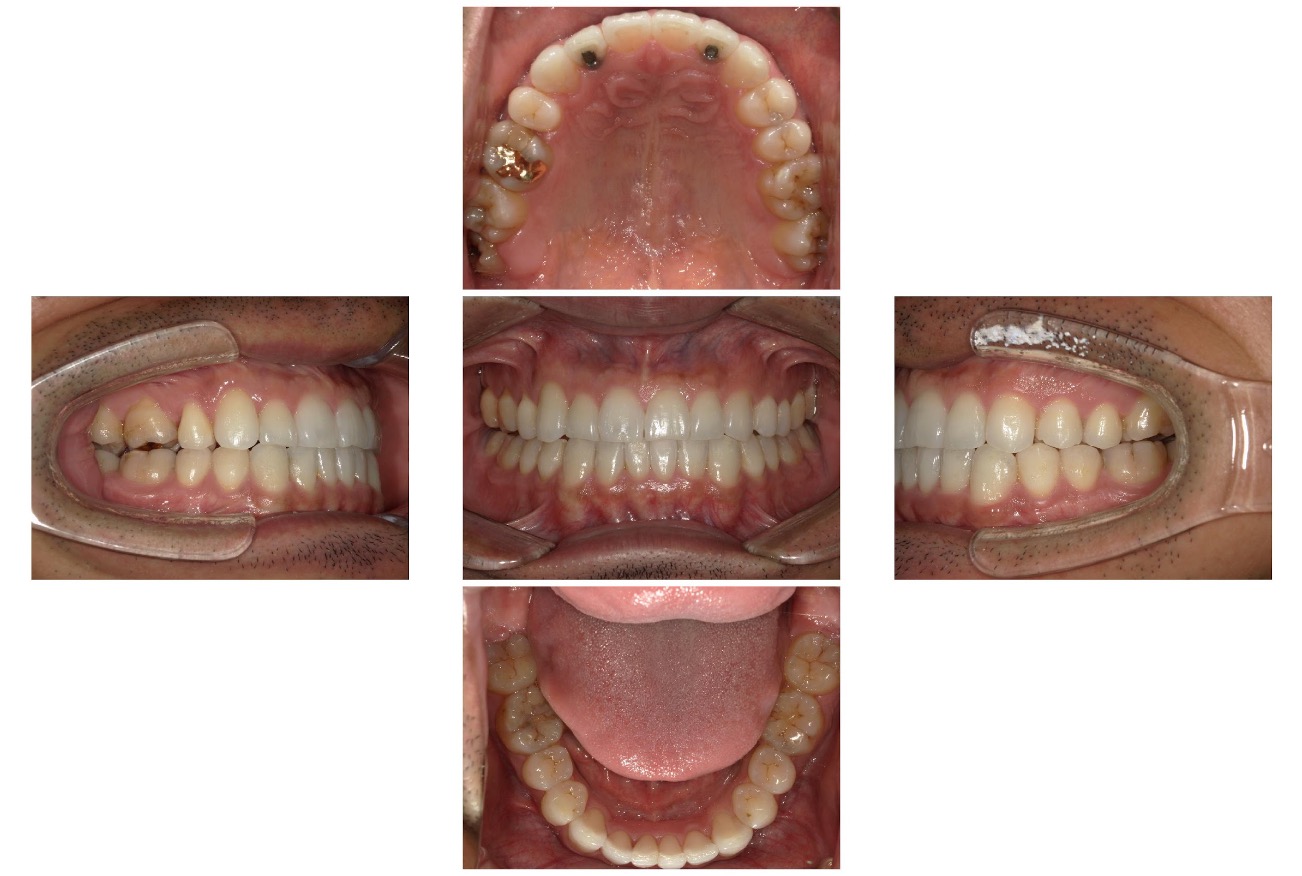

Case.03

治療前

治療後

| 主訴 | 上の八重歯と、上下の凸凹がきになる |

|---|---|

| 治療 期間 | 2年 |

| 治療費 | 880,000円 (税込968,000円) |

| 治療 内容 | インビザライン 右上3、左上3、右下4、左下4 抜歯 顎間ゴム |

| 治療の リスク | 1日に20時間以上装着しないと、予定通りに歯が動かないことがあります。装着後数日痛みがあります。 |